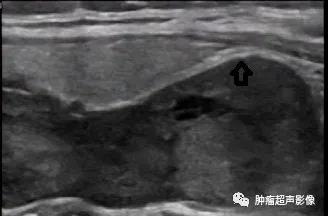

巨大甲状旁腺腺瘤位于甲状腺背侧,形态不规则,完整的包膜,与甲状腺相邻处见双包膜(箭头示),呈低回声,血流丰富杂乱。